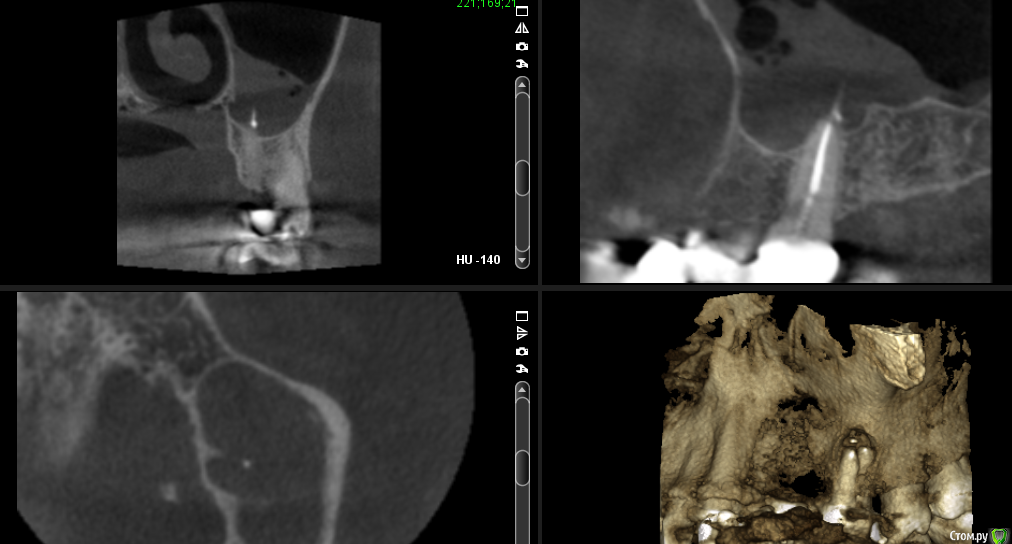

___49___ Опубликовано 29 августа, 2016 Автор Поделиться Опубликовано 29 августа, 2016 Мне необходимо мнение ваше - коллег ....оно совпадает с моим)) , До КТ надеялся, что изменения только у апексов щечных корней верхней трети, без вовлечения пазухи и небного корня....но не тут то было . . Ссылка на комментарий